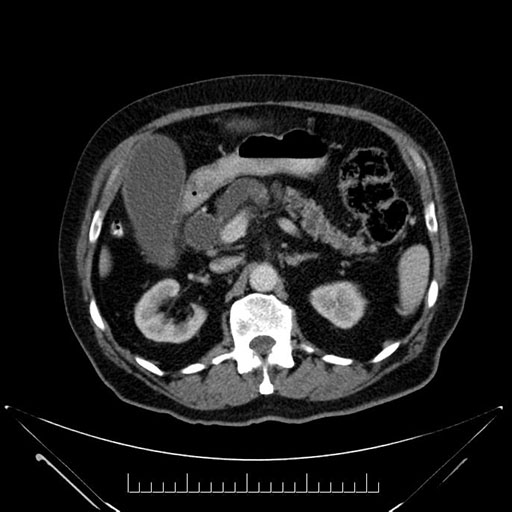

Imaging Analysis

Look through the patient's CT scan to identify any areas of concern for the necessary procedure.

Based on your CT findings, which issue(s) would give reason for "planned slowing down moment(s)" in this case?